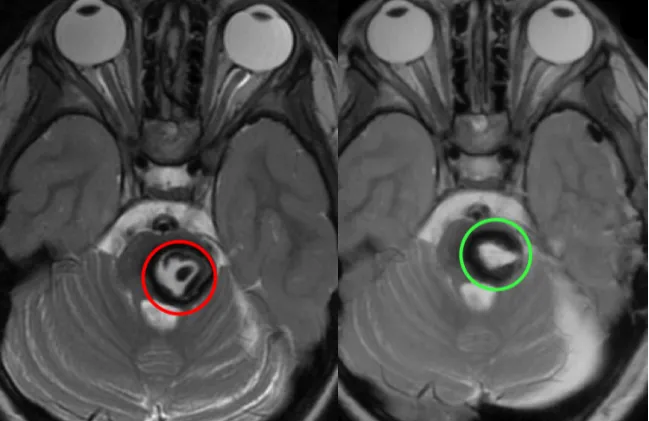

图示:术后MR复查证实病变全切,瘤腔内高信号为止血材料(红色标示术前,绿色标示术后)。